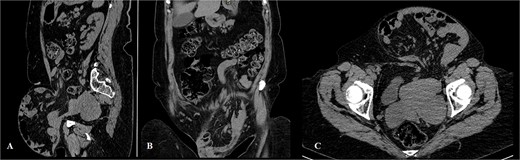

The physical exam revealed an irreducible giant abdominal wall hernia (mostly on the left lower part of the abdominal wall). Due to irreducibility, the hernia defect was not accessible for palpation and estimation. A previous low midline laparotomy scar was visible (Fig. 1A and B). A computerized tomography diagnostic scan of the abdomen was performed. It presented with a hernia defect (65 mm in width) in the left inguinal region (Fig. 2A–C).

Clinical appearance of the hernia (A – view from below, B – frontal view).

Computerized tomography of the abdomen (A – sagittal scan, B – coronal scan, C – axial scan).